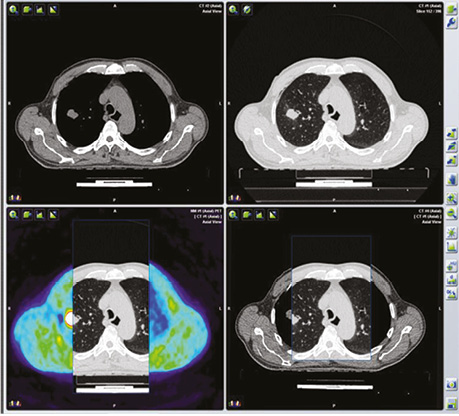

10 пацієнтів, яким діагностичне дослідження провели з ПЕТ / КТ з 18F-ФДГ, також були проліковані за допомогою таргетної терапії препаратом Нексавар®.

В якості ілюстрації наводимо клінічні випадки виконання ПЕТ / КТ з 18F-ФДГ у хворих з йод-негативними вогнищами ДРЩЗ з метою діагностики та постлікувального моніторингу.

Хворий А., папілярний рак щитоподібної залози, 4 курси РЙТ, відсутність накопичення 131I-NaI на постлікувальному скані після 3-го курсу. За даними УЗД та КТ обстеження — підозра на можливі вогнища в зоні шиї та легень. Хворому назначено ПЕТ / КТ з 18F-ФДГ (рис. 4, 5).

Діагностичне сканування з 18F-ФДГ допомогло виявити зниження функціональної активності вогнища в зоні шиї (SUV — 6,9–4,2). Зменшення розміру вогнища не відмічалося (рис. 6).

Рис. 6. ПЕТ / КТ з 18F-ФДГ. Вогнище гіперфіксації 18F-ФДГ у надключичній зоні справа, метаболічне зображення після проведення таргетної терапії

Наступним етапом була таргетна терапія йод-негативного метастатичного вогнища в легені. Для оцінки результативності лікування проведено ПЕТ / КТ з 18F-ФДГ. За даними метаболічного сканування достовірних змін як щодо розмірів вогнища, так і ступеня його функціональної активності не виявлено.

Так, проведення досліджень з одержанням метаболічних зображень у пацієнтів з йод-негативною формою ДРЩЗ до та після проведення таргетної терапії дозволило оцінити її ефективність як за розмірами метастатичного вогнища, так і рівнем його функціональної активності.